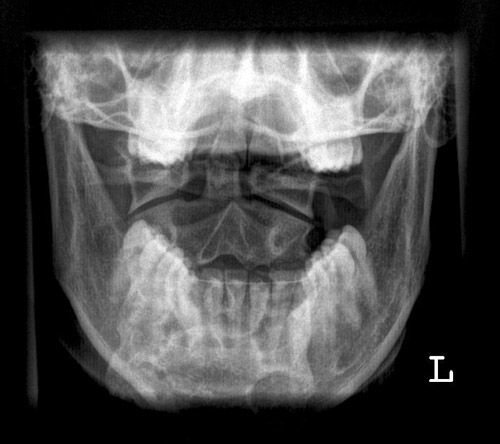

HWS

Dens a.p.

Fehler

Überlagerung des Atlas und der Densspitze durch die Hinterhauptschuppe. Die Bissfläche der Zähne des Oberkiefers bilden sich weit oberhalb der Densspitze ab.

Abhilfe

Kinn geringfügig stärker gegen den Hals anziehen lassen.